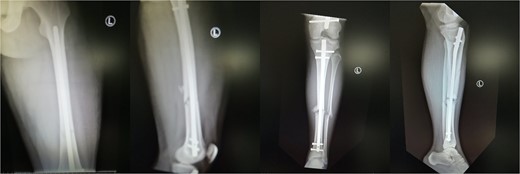

A 19-year-old male patient was admitted to the orthopedic department of our institution after a motorbike accident. The patient sustained a diaphyseal fracture of the left femur and ipsilateral tibia (floating knee) (Fig. 1), along with a right acromioclavicular joint type II injury and a right minimally displaced distal radius fracture. The patient was scheduled for emergent surgery. He underwent a retrograde intramedullary nailing of the left femur and an antegrade intramedullary nailing of the left tibia, under general anesthesia (Fig. 2). The operation was performed with the patient in the lithotomy position. The right intact leg was applied in 1000 of the hip flexion and 900 of the knee flexion. The duration of the surgery was 4 h and 20 min.

Ipsilateral femoral and tibial shaft fracture of the left limb (floating knee).